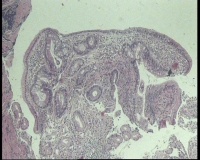

请老师看看胃角溃疡,上皮有轻度非典型增生吗?

性别年龄58岁临床诊断胃角溃疡

一般病史胃角:近后壁见一处圆形溃疡,大小0.6x0.6厘米,底附黄白苔,周围粘膜充血水肿

标本名称胃镜活检

大体所见胃镜活检组织

镜下胃粘膜腺体肠化,局灶腺上皮细胞核大

有坏组织,符合溃疡,腺体肠化,轻度不典型增生。

溃疡+萎缩+肠化+修复。

有肠化和修复性增生。